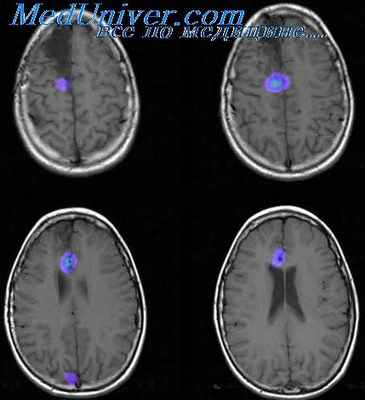

Из инструментальных методов исследований наиболее эффективным для выяснения морфологических основ ФЭ является МРТ. Толщина срезов должна составлять около 1-2 мм, чтобы как можно точнее обнаружить мельчайшие дефекты вещества головного мозга. В случае симптоматической эпилепсии МРТ даёт возможность выявить первопричину: очаговые поражения, атрофии, дисплазии. В ряде случаев обнаружить подобные изменения не удается и тогда диагноз - идиопатическая или криптогенная ФЭ. В качестве дополнительного, но необязательного исследования может быть назначена ПЭТ головного мозга. ПЭТ зафиксирует эпилептогенный участок как зону повышенной метаболической активности. ОФЭКТ также применяется в качестве дополнительного метода диагностики, в ходе которого специалист способен отслеживать динамику перфузии церебрального вещества: в течение припадка будет наблюдаться картина гиперперфузии эпилептогенного очага, а в отрезок времени между пароксизмами - гипоперфузия.